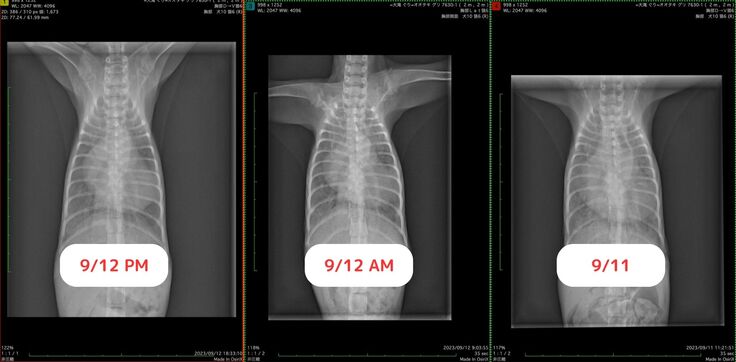

今回の入院中のレントゲン写真です。

パンパンだった心臓も少し小さくなり、肺も白さが薄くなりました!

呼吸も乱れたし、どうなることかと思いましたが、なんとか生きています…!